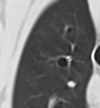

What are the three general causes of bronchial dilation/bronchiectasis?

- Damage to bronchial wall (e.g., chronic bronchitis, chronic pneumonia)

- Obstruction of the bronchial lumen

- Traction from fibrotic tissue (e.g., IPF)

What is the significant feature present in this image that helps you identify the type of bronchiectasis present?

- No bronchial wall thickening to indicate chronic inflammation/damage

- Too diffusely affected to be secondary to obstruction of the lumen

- Diffuse ground glass opacity may indicate pulmonary fibrosis –> therefore this is traction bronchiectasis.

Fitzgerald, et al. VRU 2017